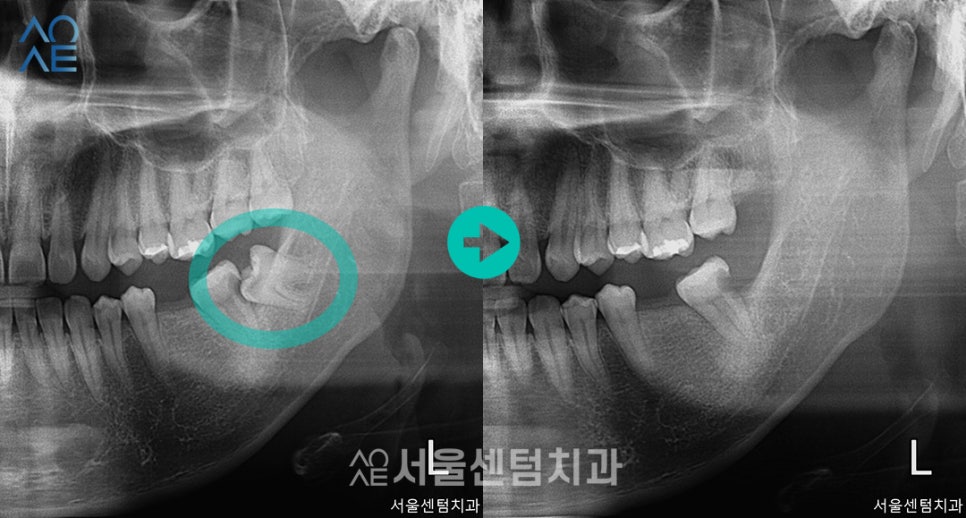

- 임플란트 치료 시작

치근단 엑스레이도 촬영해서 진단한 결과

이미지에 표시한 사랑니로 인하여

옆 치아까지 문제가 생겼다고 볼 수 있었습니다.

이러한 경우 치아를 다시 살리는 것은 불가능하기 때문에

발치 후 임플란트를 식립해야 합니다.

사랑니가 올바르게 나오고 잘 관리가 되면 다행이지만

이렇게 인접 치아를 손상시키기도 합니다.

또 안쪽에 있어서 충치나 잇몸질환이

발생하기도 하기 때문에 발치하는 것이 좋습니다.